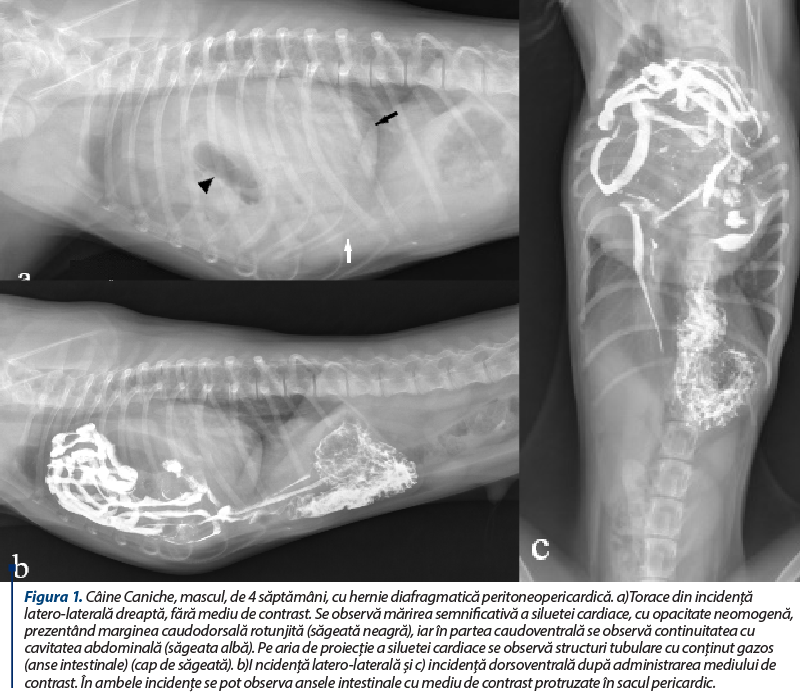

Diagnosticul se stabileşte pe baza modificărilor constatate pe imaginile radiografice (figura 1). Examenul radiografic al toracelui evidenţiază mărirea siluetei cardiace şi prezenţa organelor abdominale în sacul pericardic, precum şi imposibilitatea diferenţierii imaginii caudale a siluetei cardiace de imaginea diafragmei, modificări decelabile pe ambele incidenţe (latero-laterală şi dorsoventrală). Pe incidenţa latero-laterală se poate constata că traheea este deplasată dorsal, iar silueta cardiacă prezintă o continuitate cu diafragma, în partea ventrocaudală. În plus, se poate constata rotunjirea marginii caudodorsale a siluetei cardiace şi prezenţa unei bandelete cu opacitate de ţesut moale, cu aspect curbiliniu, care se extinde de la marginea caudală a siluetei cardiace la diafragmă, reprezentând o rămăşiţă a mezoteliului peritoneopericardic dorsal(2). Silueta cardiacă prezintă o opacitate eterogenă, iar în cazul în care ansele intestinale conţin gaz, pe aria de proiecţie a siluetei cardiace se pot observa segmente tubulare sau circulare radiotransparente, ceea ce facilitează stabilirea diagnosticului (figura 1a). Prezenţa anselor intestinale în sacul pericardic reprezintă un semn patognomonic pentru hernia diafragmatică peritoneopericardică. Ca urmare a hernierii organelor abdominale în sacul pericardic, abdomenul poate avea un volum mai redus. Pe incidenţa dorsoventrală se constată aspectul rotunjit al siluetei cardiace şi suprapunerea marginii sale caudale peste diafragmă. În urma administrării mediului de contrast se poate evidenţia prezenţa unor segmente gastrointestinale protruzate în sacul pericardic (figura 1, b şi c).

Figura 1. Câine Caniche, mascul, de 4 săptămâni, cu hernie diafragmatică peritoneopericardică. a)Torace din incidenţă latero-laterală dreaptă, fără mediu de contrast. Se observă mărirea semnificativă a siluetei cardiace, cu opacitate neomogenă, prezentând marginea caudodorsală rotunjită (săgeată neagră), iar în partea caudoventrală se observă continuitatea cu cavitatea abdominală (săgeata albă). Pe aria de proiecţie a siluetei cardiace se observă structuri tubulare cu conţinut gazos (anse intestinale) (cap de săgeată). b)I ncidenţă latero-laterală şi c) incidenţă dorsoventrală după administrarea mediului de contrast. În ambele incidenţe se pot observa ansele intestinale cu mediu de contrast protruzate în sacul pericardic.